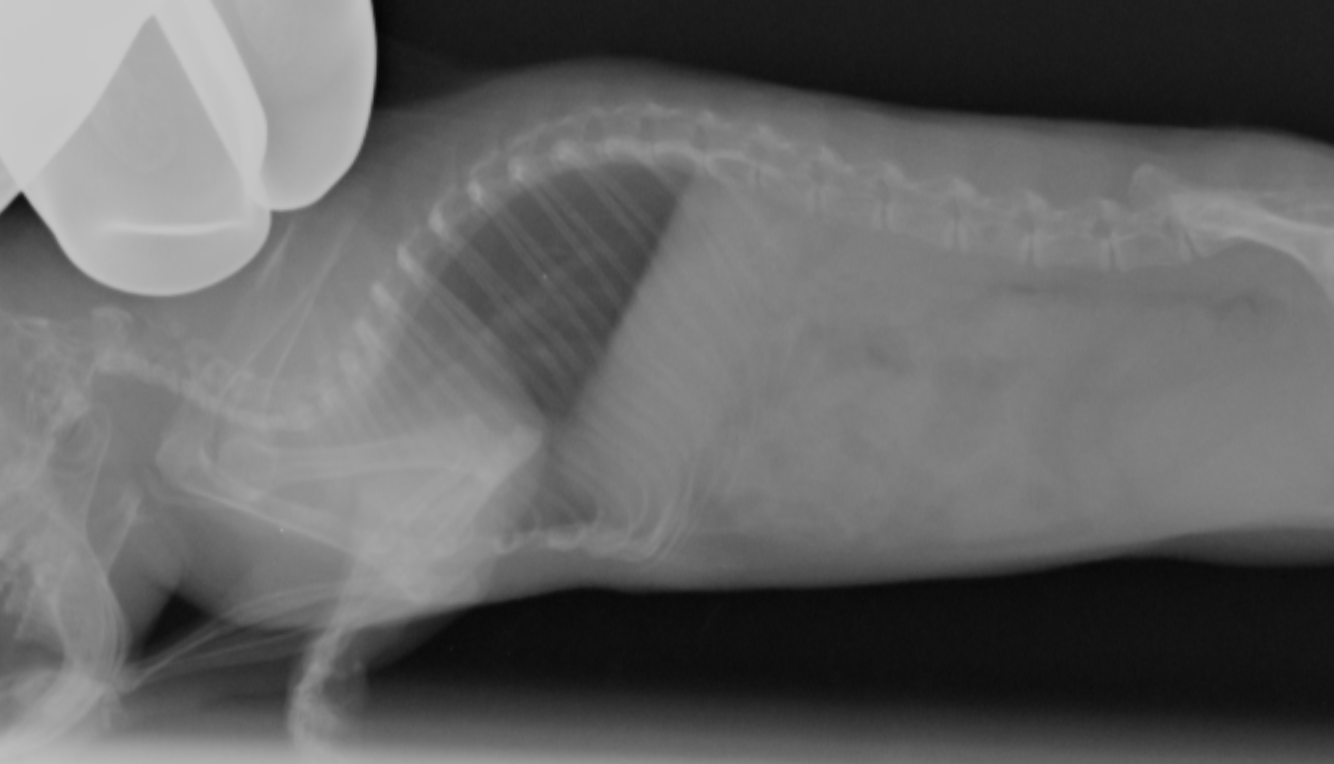

あまり綺麗なポジショニングではないですが、正常例です

同じく心筋症

正常画像と比べ明らかに心臓が拡大しているのがわかります。また肺の領域も白く見え肺水腫もしくは胸水の存在が疑われます。